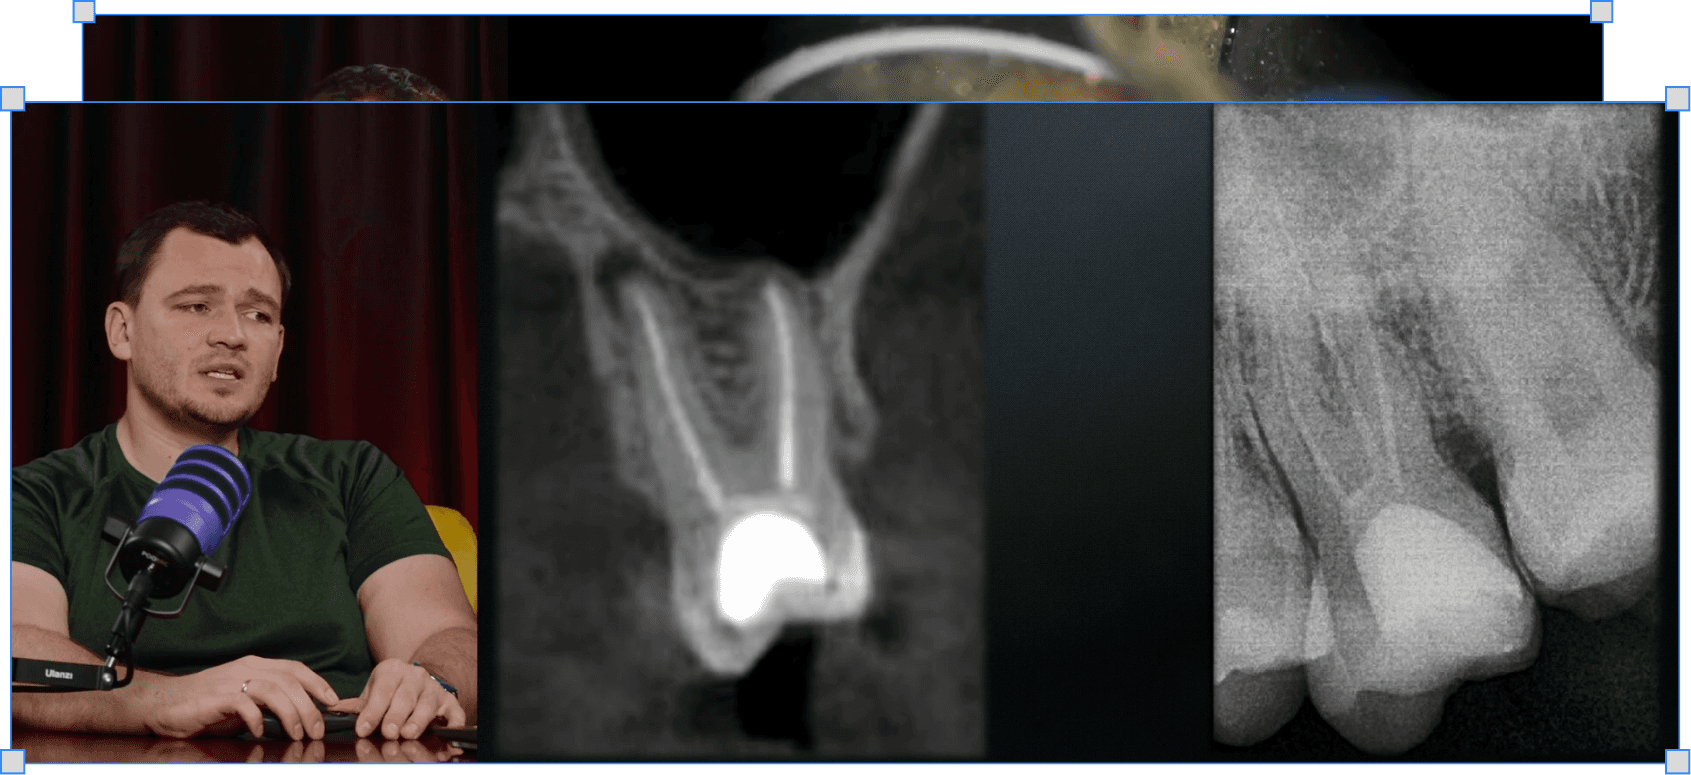

Краундаун, робоча довжина і вибір інструменту — три речі які вирішують чи подзвонить пацієнт вночі

Як вибирати робочу довжину без загострення

Чому між нулем і мінус одним є різниця — і як вона впливає на результат

Як вибирати інструмент щоб мінімізувати екструзію

Які характеристики інструменту мають значення і на що дивитись при виборі